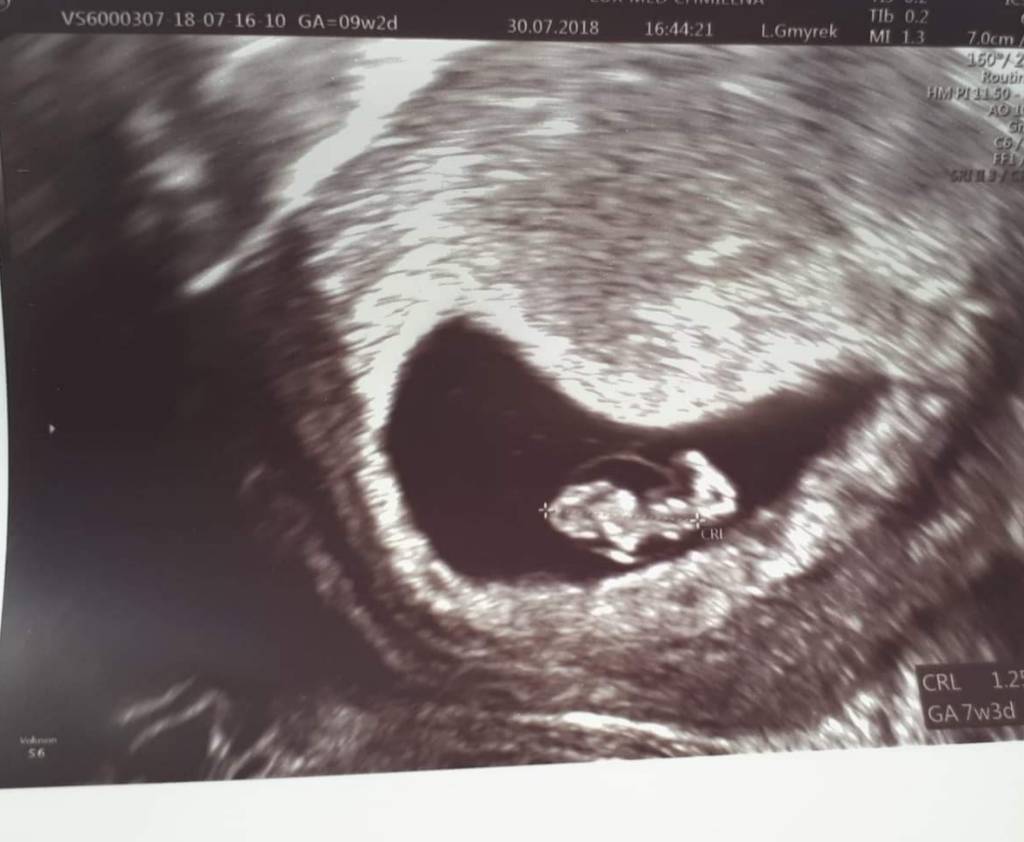

Junior ma 13 mm

7+4

TP 15 marca

Serduszko 155

20180730_164242.jpeg

Serduszko 155 Zobacz załącznik 882994